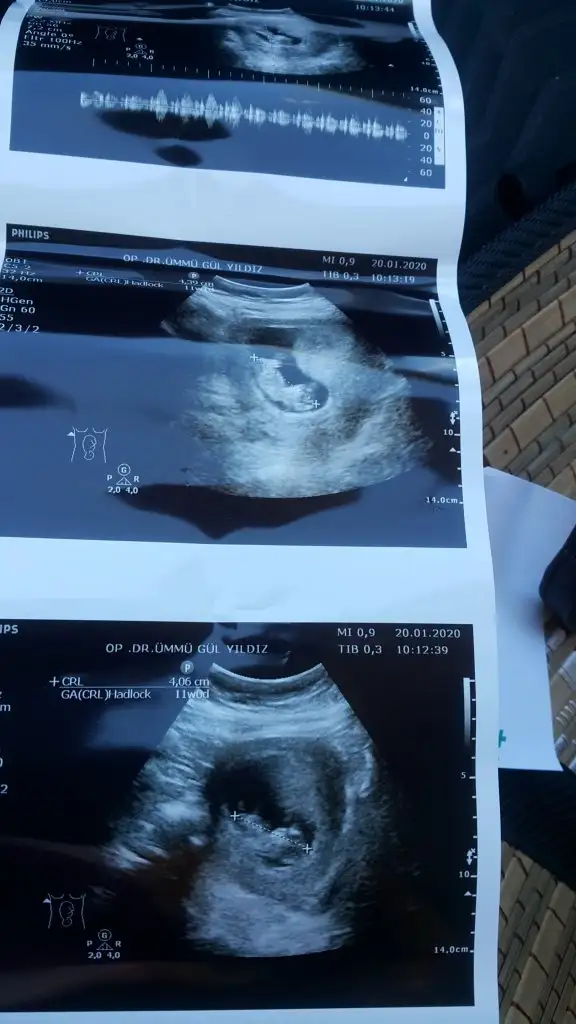

Sevgili İkra,

Yorumlarsan çok sevinirim. ☺️❤️